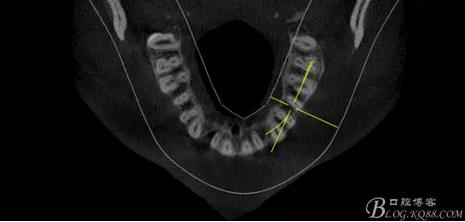

(1) 檢查:12唇側(cè)牙齦可見竇道,牙體顏色較鄰牙暗,無光澤,形態(tài)完整無缺損,唇側(cè)及近遠中向未提及牙周袋。腭側(cè)齦緣輕度紅腫,舌側(cè)窩可探及裂溝,可見浸墨狀痕跡,沿裂溝舌側(cè)探診牙周袋深大于11mm,除患牙外全口牙周狀況良好,為探及牙周袋,牙齦色粉紅。邊緣菲薄,質(zhì)地堅韌。12冷熱診無反應(yīng),叩診(+-),無明顯松動,無咬合創(chuàng)傷。12根尖x線片示,根管中三分之一中可見一斜向線樣透射影像根尖區(qū)及遠中根三分之一可見低密度透射暗影,錐形束CT示12根尖區(qū)唇腭向骨吸收已穿通,根面溝達根中三分之一卷曲分出另一牙根,再未見其他明顯的根管系統(tǒng)。